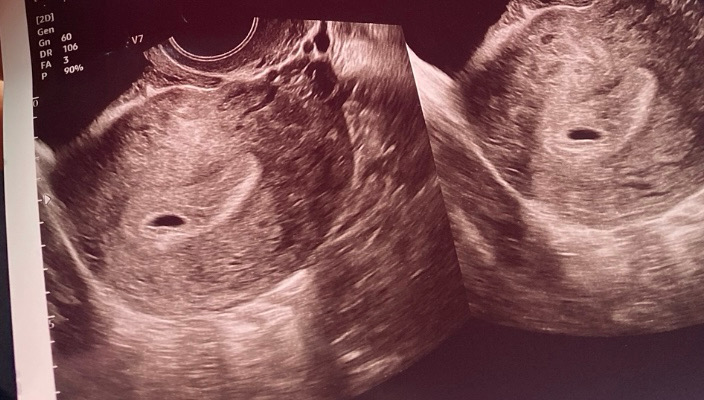

첫 초음파!

1/1생리 시작일이고, 18일에 5일 배양 이식했어요! 시험관 1차는 로또라던데 로또가 찾아왔네요🥺 1차, 2차 피검 무사 통과하고 드디어 오늘 아기집 보고 왔어요! 우리 같이 건강하게 만출해요!!!!!🫶 혹시 국민행복카드는 어디에서 발급받으면 좋을까요..? 미즈톡톡보단 베베폼에서 발급 더 많이 하시나요? 처음이라 아무것도 몰라 고민투성이에요😭😭😭